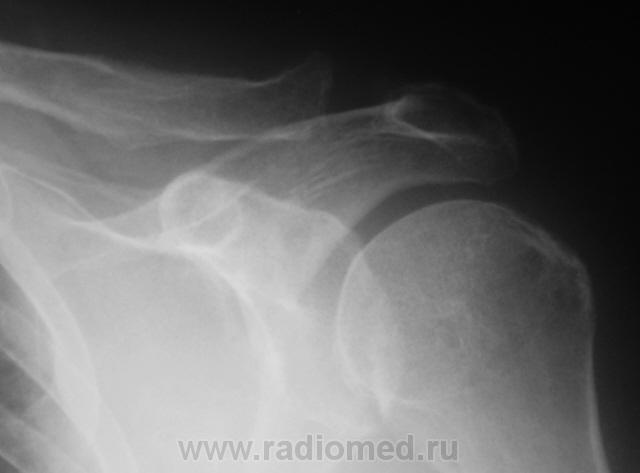

Травма. Пациент направлен на рентгенографию плечевого сустава.

Изменения АКС и большого бугорка головки плеча из разряда ревматических заболеваний с агрессивным синовиитом.

Разрыв акромиально-ключичного сочленения?

Да, щель АКС широкая, но нет подвывиха ключицы вверх. Хирургам же нужен симтом "клавиши".

Тогда левый для сравнения? Щель то слишком широкая. Мы же не хирурги.

Ширина щели АКС вариабельна, видела и достаточно широкие-1.2 см.Приходится второй делать для сравнения.В верхне-наружном квадранте плечевой кости что-то типа "пробойника"и компактный костный островок? Снимки плохо открываются..